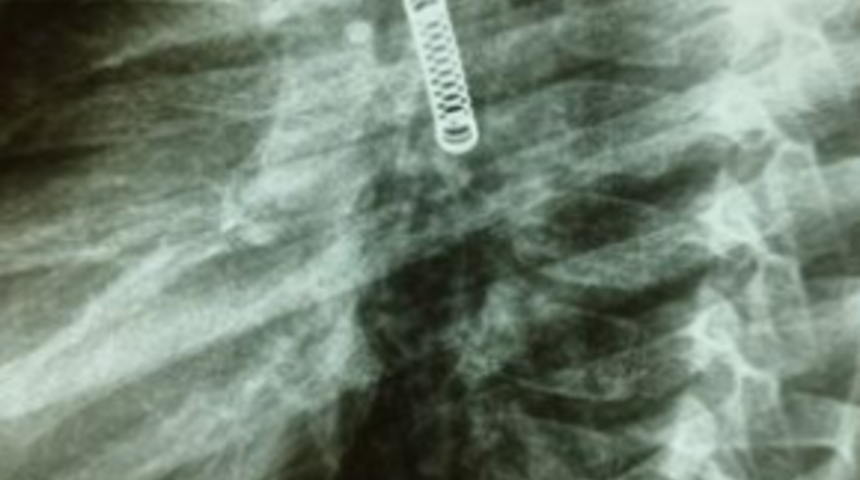

Paraguay’da yaşayan ismi açıklanmayan 5 yaşındaki bir çocuk ailesi onu doktora götürmeye karar vermeden önce 3 ay boyunca sürekli olarak öksürüyordu. Adı açıklanmayan çocuk ilk olarak Regional De Villarrica Hastanesinde tedavi altına alındı ve daha sonra acil tedavi için Ulusal Solunum ve Çevre Hastalıkları Enstitüsüne nakledildi. Yapılan incelemeler sonucunda sağlık görevlileri 5 yaşındaki çocuğun sol akciğerinde metal bir cismin olduğu fark edildi.

Operasyonu gerçekleştiren Dr. Carlos Morinigo, yabancı cismin çocuğun akciğerine yerleşme şekli ve zamanı değerlendirildiğinde prosedürün karmaşık olduğunu dile getirdi. Dr. Morinigo prosedürün başarılı bir şekilde tamamlandığını ve küçük çocuğun zamanla eski sağlığına kavuşabileceğini ifade etti.